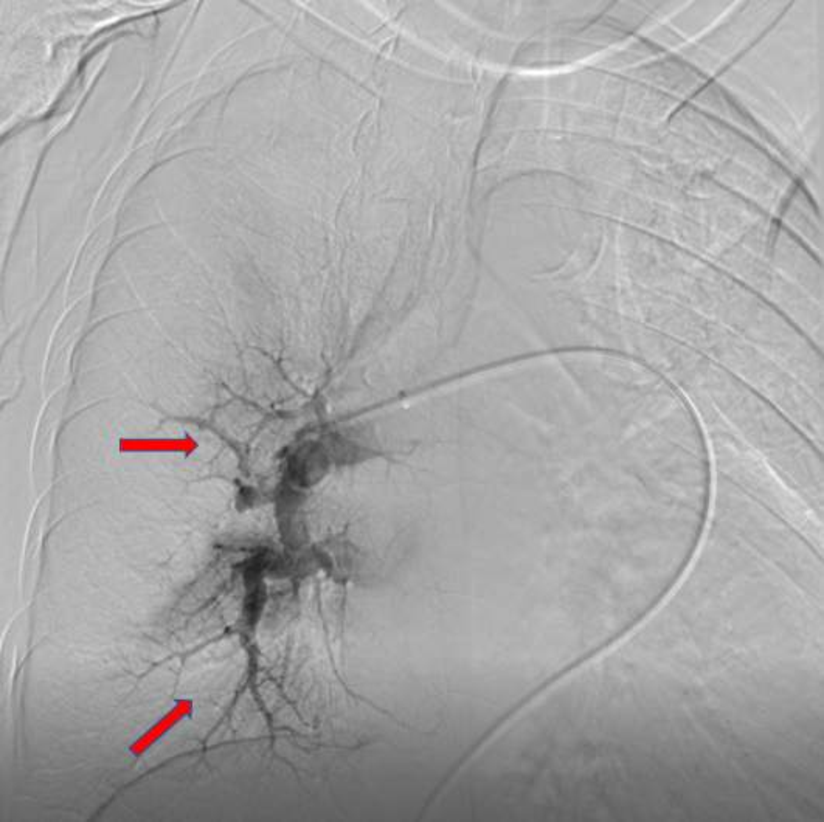

下肢静脉彩超提示双侧小腿多支静脉血管血栓形成。心超彩超示重度肺动脉高压(肺动脉收缩压101mmHg),右心明显增大,TAPSE:1.68cm,少量心包积液(图2)。肺动脉CT(CTPA)示主肺动脉及右肺动脉干明显增宽,右肺动脉干见巨大充盈缺损,叶、段肺动脉均未显影;左侧肺动脉多发分支充盈缺损(图3)。肺动脉造影提示右肺动脉叶段分支均未显影(图4)。

图4 左图为本患者肺动脉造影图,右图为正常肺动脉造影参考图

综合以上情况,考虑肺栓塞(考虑慢性肺血栓,本次急性发作)、慢性血栓栓塞性肺动脉高压、心力衰竭、呼吸衰竭诊断,病情危重,随时可能猝死。考虑血栓负荷大,给与肺动脉吸栓术,术后右肺动脉叶段多支显影,见下图。